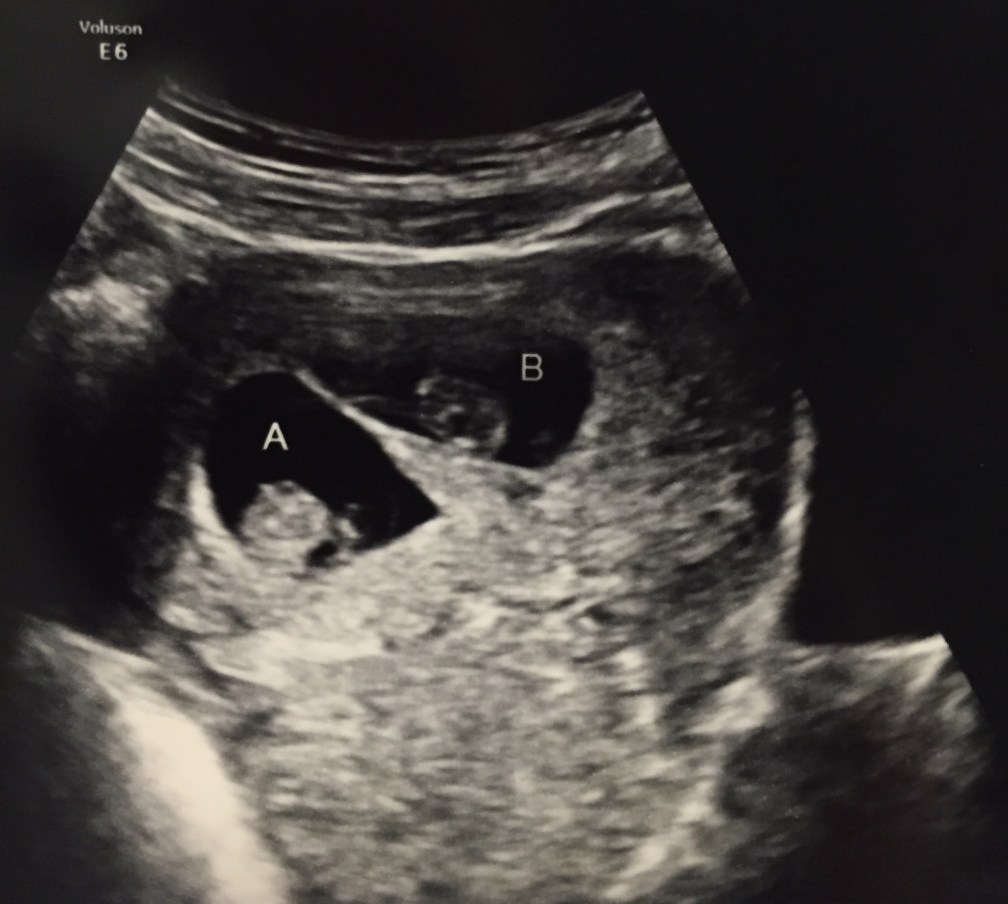

So when the technician turned on the screen and began the ultrasound I knew what to expect. A small black circle (the sack) with an even tinier speck inside.

That is not what I saw.

And I stopped breathing.

I saw two black circles with tiny specks inside. Two embryos.

In case you didn’t pay attention in Health class, two embryos grow into two babies.

I stared at the screen in shock. When my lungs started shouting at me to breathe, my body tried to play catch up and I began breathing really quickly. Too quickly.

Three weeks later, I walked into the doctor’s office mentally prepared for bad news. Your dad held my hand as they started the ultrasound. Two sacks popped up right away. I know this is going to sound strange, but I felt relieved, overwhelmed and numb all at the same time.

When the nurse took us back I was still crying. The tears continued to flow when the doctor came in and said both babies looked great and were measuring the same size. She wasn’t worried about “Baby B” anymore. She said she was more worried about me than the babies. ha!